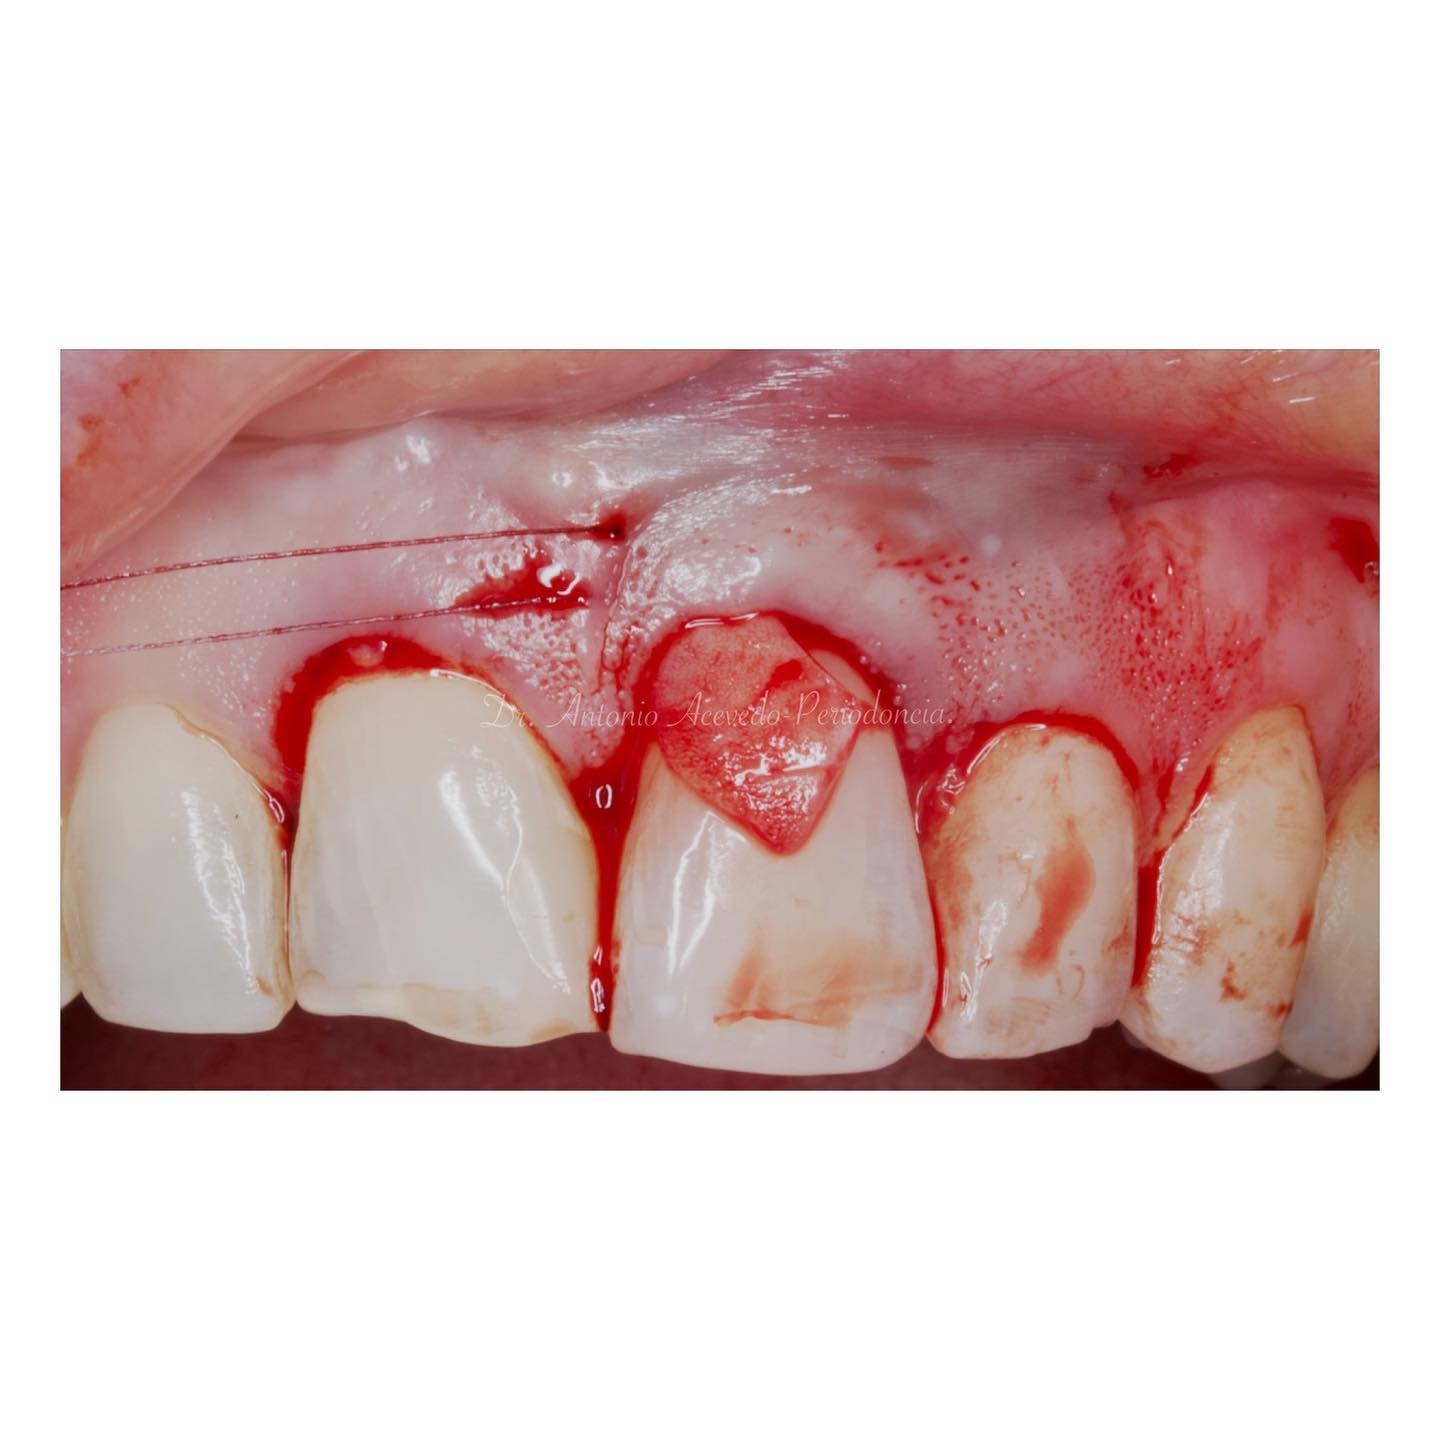

Durante una mañana, asistirás a una Cirugía Mucogingival de recubrimiento radicular de recesiones múltiples en IV y V sextante (36 a 43).

Se realizará todo el procedimiento con un microscopio operatorio, lo que permite al alumno ver toda la cirugía en directo en una pantalla en la sala de cirugía.

Aprende la planificación y técnica de la cirugía Mucogingival para el recubrimiento de recesiones y aumento de banda queratinizada en el sector anteroinferior

La formación comenzará con la presentación del caso clínico que se abordará durante el curso, seguida de una cirugía en directo, que permitirá observar paso a paso el procedimiento y la toma de decisiones clínicas. Durante la jornada se profundizará en los conceptos biológicos aplicados a

Durante una mañana, asistirás a una Cirugía Mucogingival de recubrimiento radicular de una recesión unitaria en 31 con frenillo asociado. Gracias al uso del microscopio y a la proyección en tiempo real en pantalla, verás exactamente lo mismo que veo yo durante la cirugía, sin tener que estar

Una estancia clínica pensada para quienes quieran iniciarse o dar un paso más en el campo de la cirugía mucogingival. Durante esta experiencia tendrás la oportunidad de aprender en directo cómo se planifica y se lleva a cabo una cirugía mucogingival mediante técnica de Túnel.

Formación teórico-práctica completa sobre las técnicas más avanzadas en cirugía mucogingival. Durante dos días intensivos, los participantes aprenderán desde la evidencia científica y la anatomía de las zonas donantes hasta la ejecución de injertos, cubrimiento radicular y aumento de

Dos cirugías mucogingivales en directo.